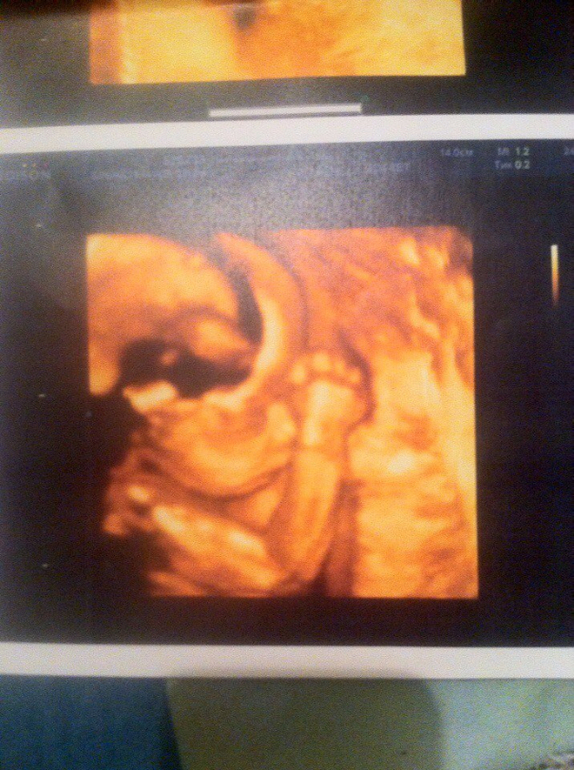

УЗИ 25 недель 1 день)

Мы вчера ходили на УЗИ в ЦИР, посмотреть кисты сосудистых сплетений, снять видео, просто полюбоваться на нашу доченьку)) Врач сказала, что девочка с характером, т.к. показываться она абсолютно отказывалась(при чем, на всех узи!! даже её появления в ПЯ мы ждали дольше, чем многие).

У нас всё хорошо ттт! Рост 29 см, вес 650 граммов. Компьютер рассчитал срок 23 недели 5 дней, врач сказала, что ничего страшного, но я всё равно немного переживаю, не страшно ли такое отставание от срока? Отставали мы всегда, правда, на первом скрининге всего на 3 дня, на втором - на 5 дней. Сейчас уже побольше((

Ну и хорошая новость - всё в норме, а главное, что кисты сосудистых сплетений головного мозга уже полностью рассосались!!!

Ну и фото нашей Королевы, и подтверждение, что она девчушка)) Хотя никто и не сомневался))